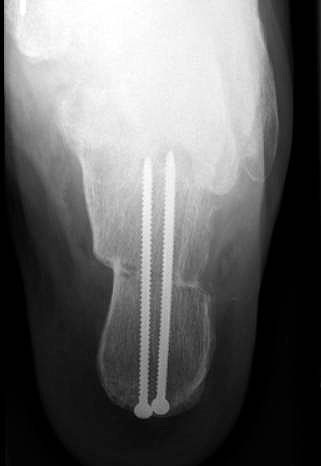

Lateralisierende Calcaneus-Osteotomie (Abb. 2 und 3, Video 2)

Die lateralisierende Calcaneus-Osteotomie ist ein Standard-Operationsschritt bei fast jeder Hohlfuβkorrektur. Der biomechanische Effekt der Osteotomie ist eine Verschiebung des Fersenkontaktpunktes und damit der beim Rückfuβ varus medialisierten Belastungsachse durch das OSG nach lateral. Diese statische Rückfuβ-Korrektur allein ist in der Lage, den bei Pes cavovarus anteromedial erhöhten OSG-Druck, der sehr wahrscheinlich zur korrespondierenden Arthrose führt, zu neutralisieren 7. Zuklappende Osteotomien mit Entnahme eines lateralen Knochenkeils haben sich dabei weniger effektiv gezeigt als solche mit Lateralisation des Tubers. Mit der Lateralisation des Achilles-Ansatzes verringert sich die Inversionskraft der Sehne zugunsten der schwachen Eversion, wodurch gleichzeitig die Prädisposition für Supinationstraumata reduziert wird. Neben der klassischen Dwyer-Osteotomie (Entnahme eines lateralen, vertikalen Keils 8 haben sich vor allem die technisch einfache Verschiebe-Osteotomien („sliding osteotomy“) und die Z-förmigen Osteotomien (Pisani 1993, Malerba 9) mit Entnahme eines lateralen Keils aus dem horizontalen Anteil der Osteotomie aber ohne Lateralisation des Tuberfragmentes, sowie die Korrektur nach Hintermann (Knupp 2008) mit zusätzlicher Lateralisation des Tuberfragmentes) durchgesetzt. Bei neutral aligniertem OSG ist keine supramalleoläre Tibia-Osteotomie zur Korrektur des Rückfuβ varus indiziert. Generell sollten Osteotomien gegenüber korrigierenden Arthrodesen der Vorzug gegeben werden. Die im Folgenden beschriebene Verschiebeosteotomie ist technisch einfach und hinsichtlich OSG-Druckneutralisation ebenso effektiv wie die Z-Osteotomien 7.

• Definitive Fixation über die dorsoplantare Querinzision mittels Schrauben (normale 3.5 mm Kortikalsischrauben sind hier völlig ausreichend).

• Kontrolle der korrekten Schraubenlage im BV (Abb. 3).